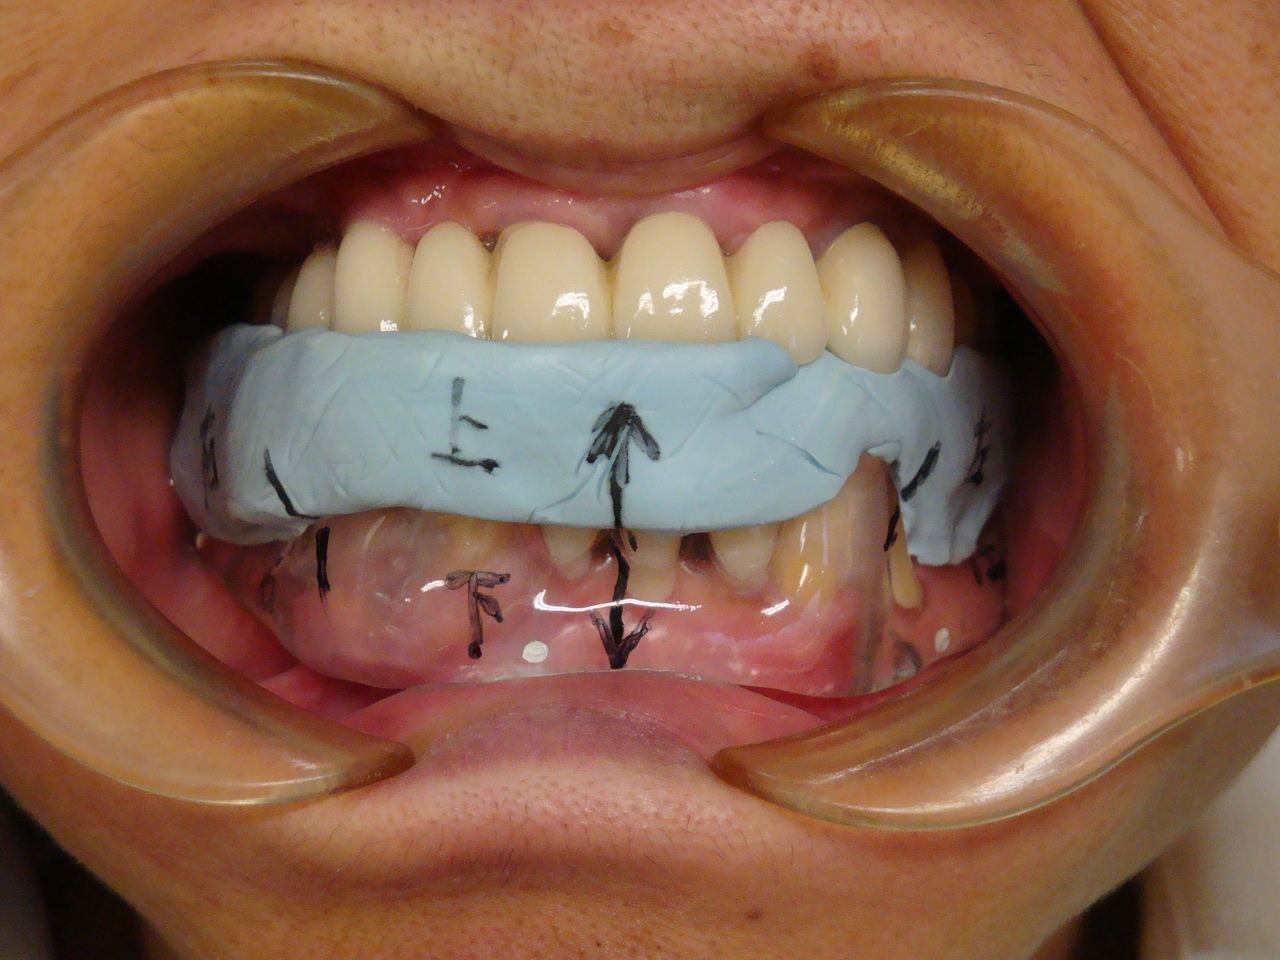

CT撮影

埋入位置を決めるための装置(ラジオグラフィックガイド)を口腔内に入れCTを撮影します。

【ラジオグラフィックガイド】

埋入ガイド

CT画像上にて決定した埋入位置で製作された埋入ガイド。正確でスムーズな手術を行えます。

【埋入ガイド】